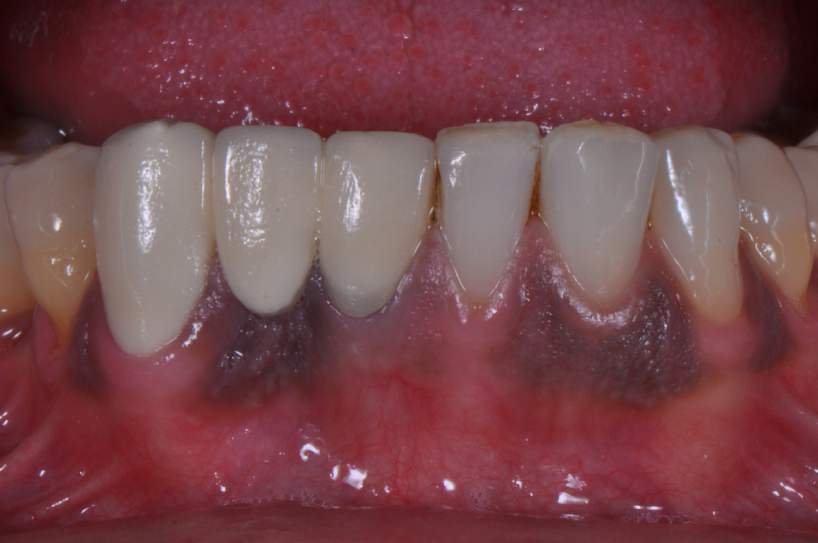

Implantes estreitos de titânio surgiram na Implantodontia com a indicação clássica de serem utilizados para substituição de incisivos laterais superiores, incisivos inferiores (Fig.1), espaços edêntulos pequenos e com baixa incidência de carga mastigatória.

Paciente com perda do incisivo central inferior do lado direito, utilizando uma prótese fixa em zircônia com estética e adaptação deficientes.